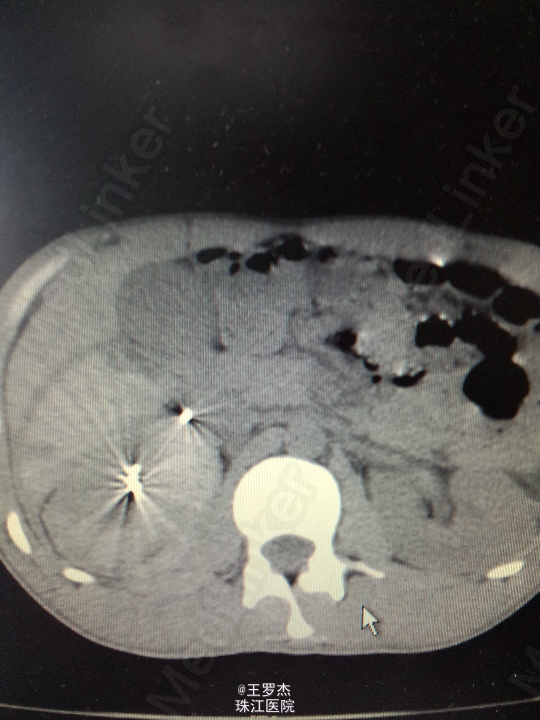

体格检查:体温:37℃,呼吸23次/分,脉率:84次/分,血压132/88mmHg。神情,查体配合。右季肋区可见3x4cm皮肤挫伤,腹部平软,双肾区无隆起,双侧输尿管走向无压痛,未触及包块,耻骨上区无充盈。 实验室检查:RBC 4.1,Hb 110g/L,WBC12.97,Cr187.0umol/L 辅助检查:CT右肾挫裂伤,包膜下大量积血,肾周、腹腔及盆腔内较多积液伴积血。

诊断治疗:右肾挫裂伤,保守治疗。3天后复查Hb89g/L,RBC2.65;复查CT提示包膜下及盆腔积血较前增多。请介入科会诊,行右肾动脉选择性栓塞。 介入:右肾挫裂伤,并上极动脉破裂出血及远端多处动静脉瘘形成,成功行超选择性病变血管栓塞术。